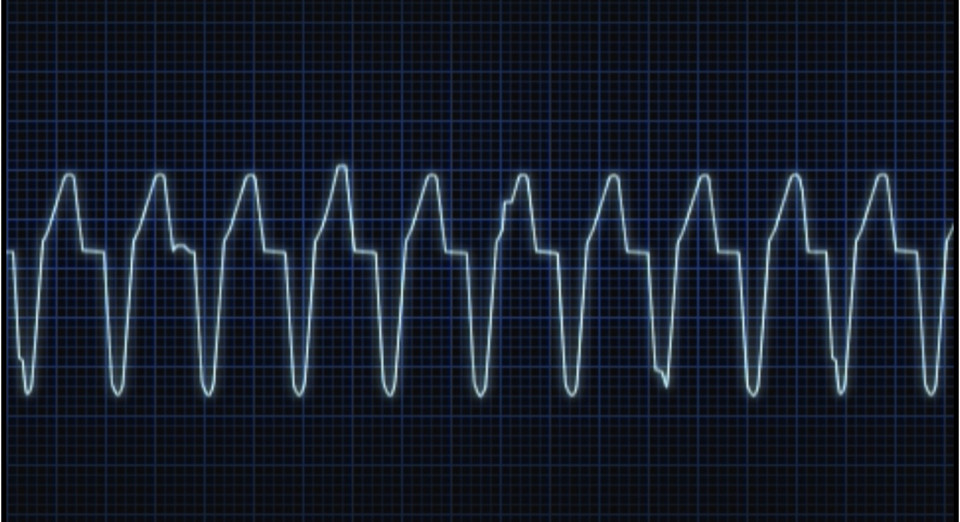

時間経過が長かったことによりショック状態

C(Circulation):循環

M(Massive hemorrhage):大量出血

C(Circulation):循環